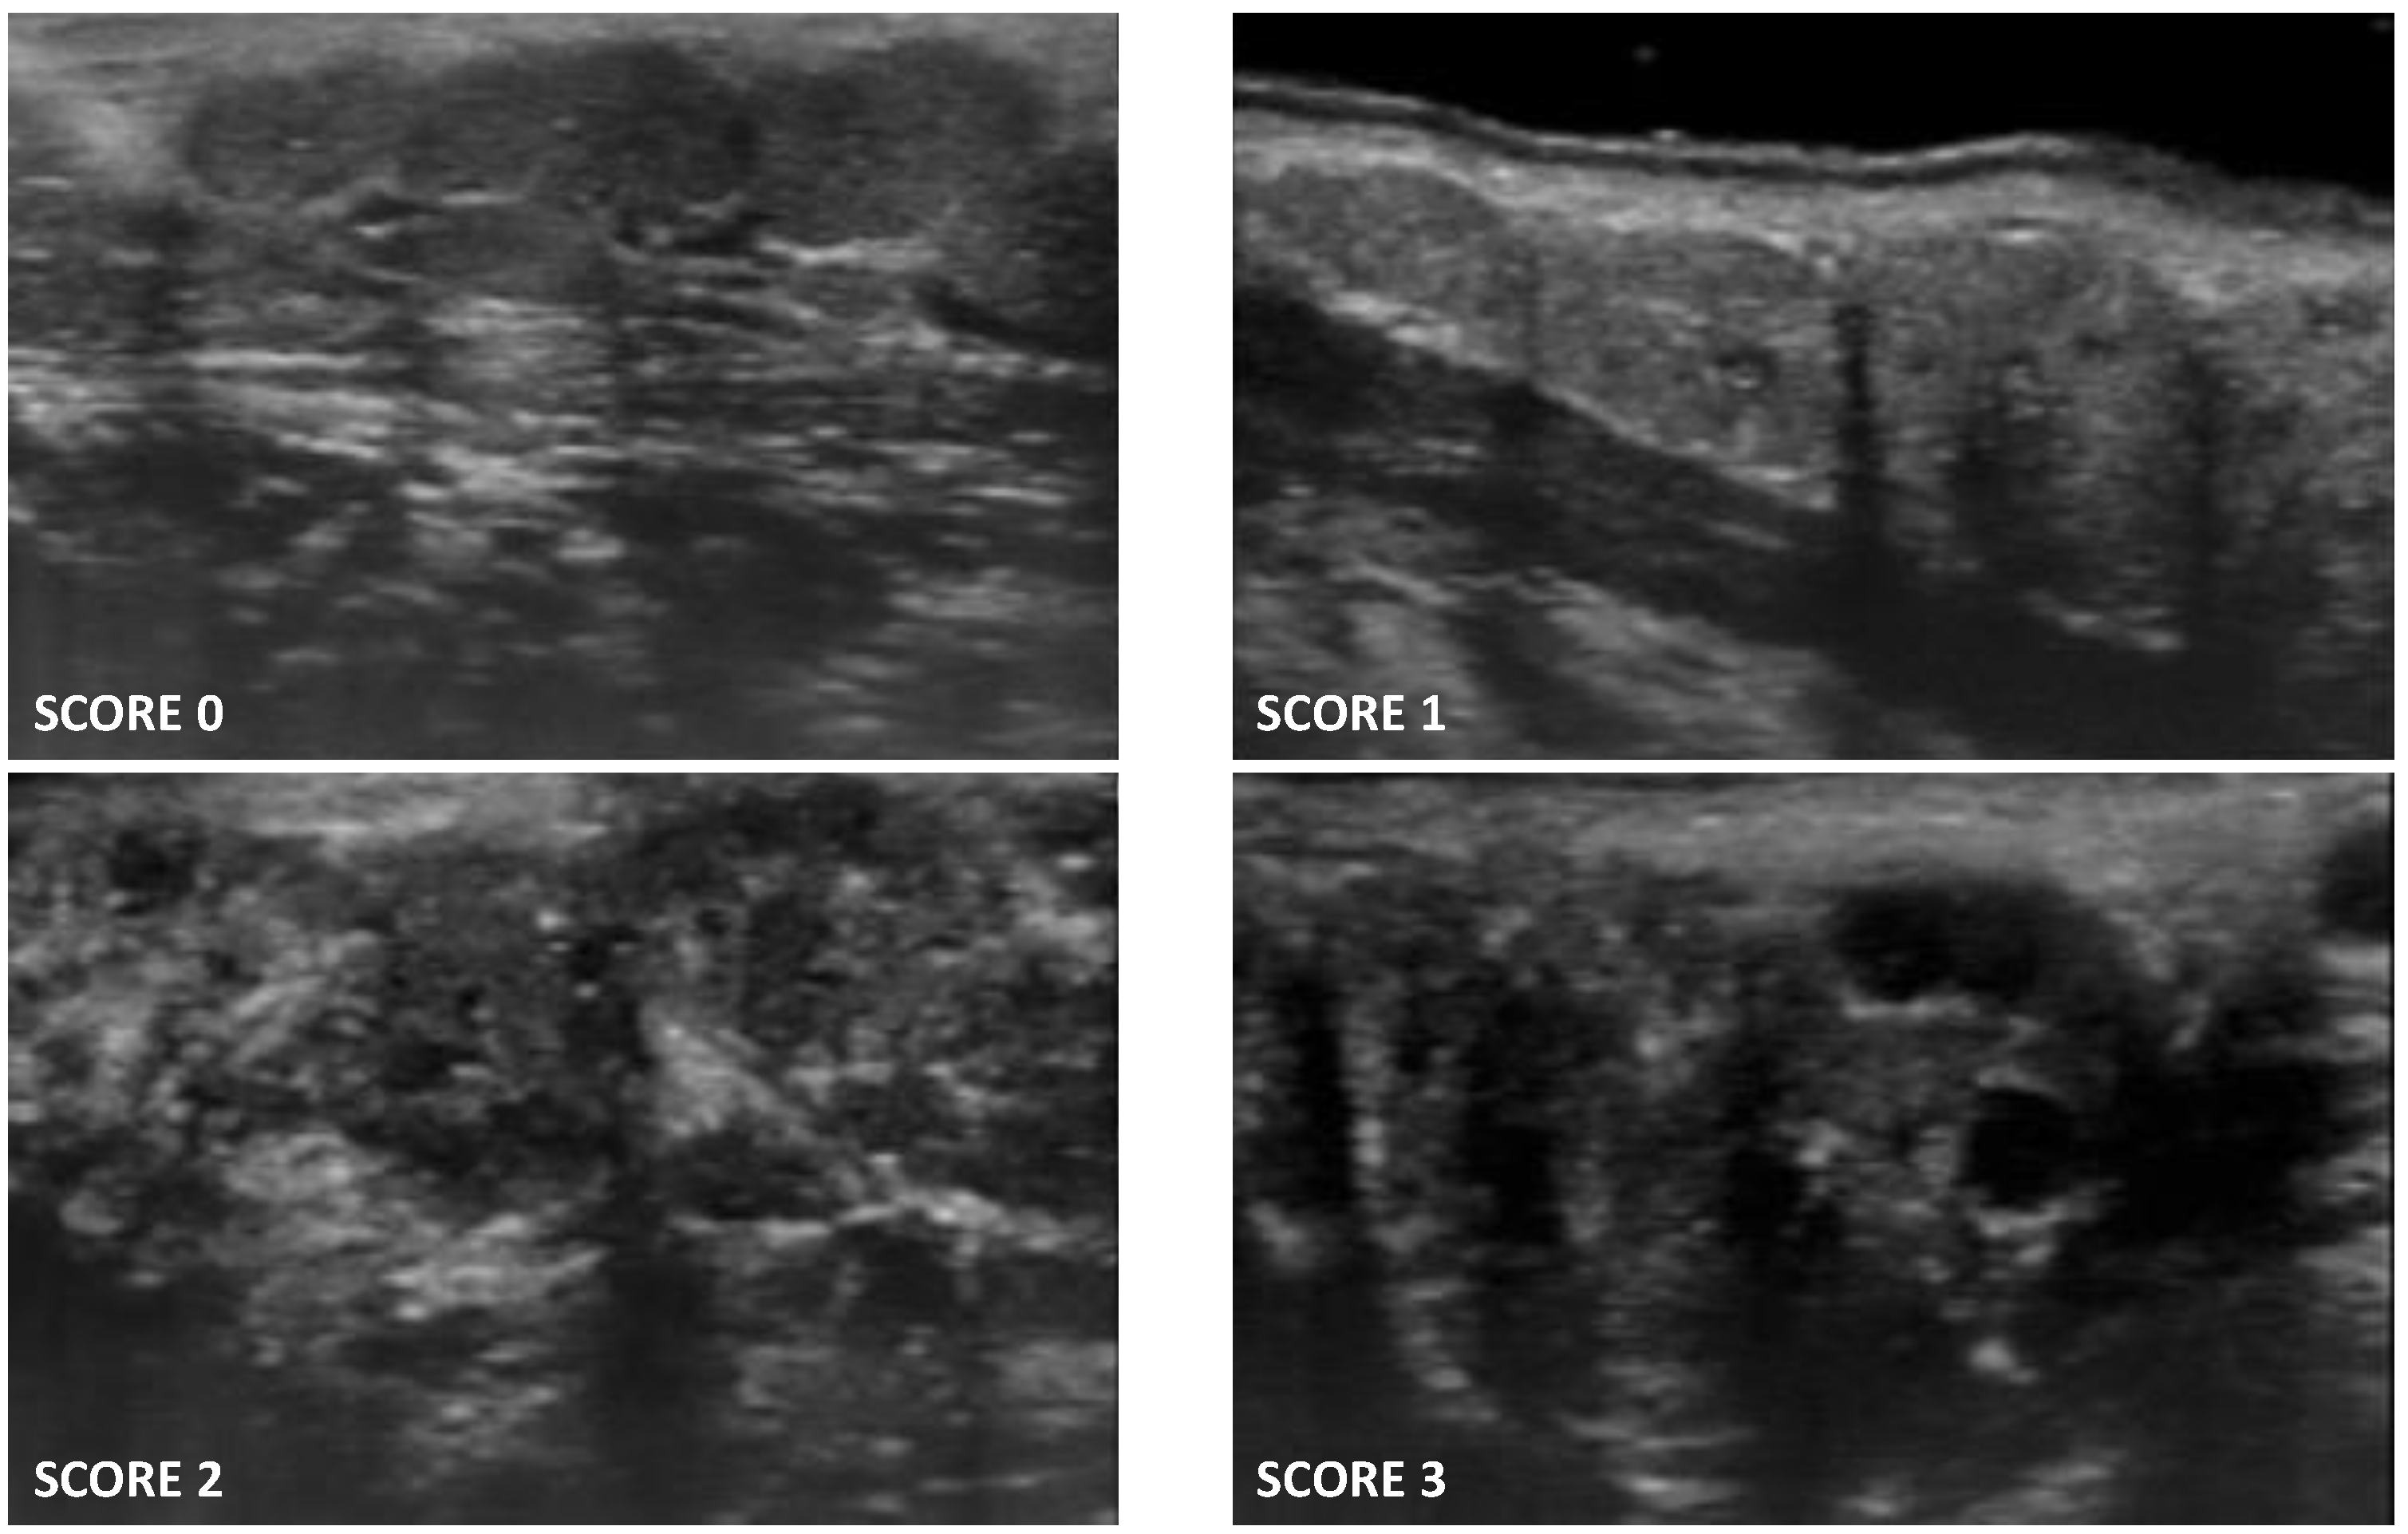

- Score 0: normal glandular parenchyma in the absence of alterations;

- Score 1: presence of fine echogenicity in the absence of clear alterations, or slight, diffuse glandular hypoechogenicity, mild glandular alteration;

- Score 2: presence of focal hypoechoic areas, but partial conservation of normal glandular parenchyma, moderate glandular alteration;

- Score 3: diffuse presence of hypoechoic areas in the absence of normal glandular parenchyma, or the presence of glandular fibrosis, severe glandular alteration.